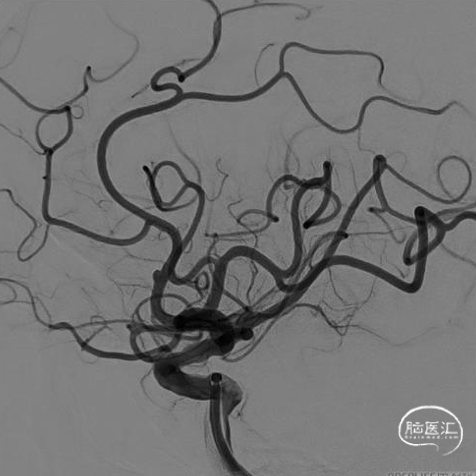

右侧颈动脉造影:海绵窦、眼段动脉瘤。

左侧颈内动脉造影:颈内动脉起始部中度狭窄,海绵窦段、床突上段多发动脉瘤。

跨弓角度大,可见赛诺神畅 6F-105 APEX TRA®经桡远端通路导引导管柔软段跨越转弯处后沿泥鳅导丝一次顺利到达岩骨段。

导管顺利到位。

术后3D造影及支架重建,可见支架展开和贴壁良好。